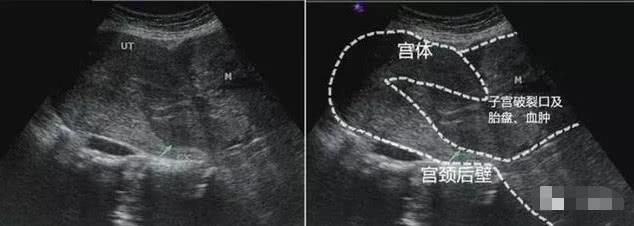

我一下就来气了,想要对她们进行教育,这时,孕妈的情况就更加严重了,我感觉不对劲,再看了一看,子宫竟然在胎儿的上方!胎儿可能不在宫腔内!很有可能是子宫破裂,这样的情况比较少,我也不是很确定,就给我们的主任打了电话,主任过来之后,再次检查,确定是子宫破裂,这个是非常严重的病情,必须赶紧采取措施,不然孕妈命就没了。手术好了之后,那位孕妈和我们说了那天的情况,原来,她想要男孩,去到了私人的医院检查B超,发现是女孩,就要求做引产,没想到手术失败了,那庸医把胎儿剪碎了也没能把胎儿取出来,导致了子宫破裂,当即这产妇就进入了ICU病房抢救。

6.完全性子宫破裂:

胎儿位于子宫内:有或无胎心搏动,子宫壁回声中断不连续,该处可有羊膜囊无回声区向外膨出,胎动时更为明显,胎盘位于子宫内,腹腔有积液,后腹膜或阔韧带处可见血肿呈低回声。

胎儿位于腹腔:多无胎心搏动;胎儿周围无宫壁回声;下腹部一侧可见收缩的子宫呈球形;胎盘可在子宫内、腹腔内或破口处;胎盘周围回声杂乱,有得可见条索状无回声区;腹腔多有大量积液。